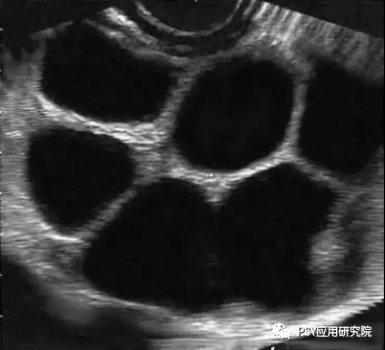

进入高温季节以后,很多猪场的配怀率开始出现下降,返情率表现上升,屡配不孕的现象有所抬头,这种情况不仅会导致母猪非正常生产天数的增加,而且也会降低猪场PSY,那么导致母猪发生高返情率的原因包括哪些呢? 图1母猪受孕后出现的不同返情时间 原因之一:发情鉴定失误 对母猪进行发情鉴定是人工授精的前提,一旦发情鉴定失误,对未发情的母猪进行授精,那么母猪将在配种后的19天之内出现返情。 发情鉴定失败的原因有二: ➤一方面是由于配种员的经验不够, ➤另一方面也与母猪的品种与个体发情表现不明显有关。 建议:在每天上午8点和下午5点,每天两次使用公猪对断奶母猪和适龄后备母猪进行辅助发情鉴定,加强对母猪发情表现的辨认度,提高发情鉴定成功率。 图2 静立反应 原因之二:霉菌毒素污染 在所有霉菌毒素中,玉米赤霉烯酮是对母猪生殖系统危害最为严重的霉菌毒素,它具有类雌激素作用,可促使母猪出现假发情,但母猪并未排卵,因此配种后又会在很短时间(多发生19天以内)出现返情。 建议:猪场加强对饲料原料的控制,尤其是在夏季母猪饲料中应降低米糠或麸皮的添加比例,控制贮存时间,可使用膳食纤维等替代品、加强对料槽、料线的清理以及添加霉菌毒素吸附剂的方法来减轻危害。 原因之三:卵巢囊肿 母猪发生卵巢囊肿以后,由于分泌过多的卵泡素,母猪性欲旺盛,经常趴跨其他母猪,但屡配不孕,其原因在于:由于母猪排卵迟滞,精子在母猪排卵之前已丧失受精能力,导致母猪受孕失败,这类返情多发生在配种后的19天以内。 建议:一旦发现母猪持续发情且屡配不孕,给母猪肌注黄体酮、促黄体素释放激素或人绒毛膜促性激素,每日1次,连用2-4次。 图3 卵巢囊肿B超图 原因之四:精液品质下降 使用不合格的公猪精液进行输精,母猪将在19-23天左右出现返情。 这种问题在夏季、秋季高发,研究发现公猪对热应激高度敏感,在环境温度超过30℃以后,无论是精子活力还是精子密度,均会出现明显下降,造成母猪受孕率大幅下降,而且公猪精液品质下降后,其恢复正常所需时间在2个月左右。 因此建议:夏季必须采取有效措施对公猪进行降温,避免热应激对公猪的不利影响,同时在饲料中添加抗应激产品,并控制公猪的使用强度,避免过度使用。 原因之五:输精时间不当 一般而言:母猪在发情后的24-36h进行排卵,排卵持续时间为10-15h,卵子保持受精能力的时间为8-10h,精子达到受精部位所需的时间为2-3h,因此最佳的输精时间为母猪排卵前的2-3h,由于输精时间不当而导致的返情多发生在配种后的19-23天。 建议:在无试情公猪条件下,可采用下表进行人工授精。 原因之六:子宫复旧不全 研究发现:母猪在分娩过程中,无论是顺产还是助产,子宫都会有不同程度的损伤,子宫复旧不全将导致母猪出现返情,一般发生在配种后的19-23天。 为确保子宫复旧完全,需要做到以下三点:尽量避免掏产,加强母猪产后护宫,在母猪产后使用宫炎净,促进子宫黏膜修复和生长;给予足够的复旧时间,确保泌乳时间不低于19天;配怀舍温度控制在24℃左右,给母猪创造良好条件。 图4 子宫复旧良好的母猪 原因之七:饲养管理不当 母猪在配种后的30天之内是胚胎死亡的高峰期,造成胚胎死亡的原因包括:各种应激(热、冷、噪音、惊吓、免疫、驱虫)、饲喂过多或过高能量饲料,研究发现:母猪建立稳定的妊娠状态至少需要5枚胚胎,低于这个数量将导致母猪在怀孕后的19-23天出现返情。 建议:在配种后的30天内,对母猪进行严格限饲,并添加青绿饲料或膳食纤维,采用“六不一优”技术,在配种的30天母猪饲喂量控制1.8-2.2kg左右,减少各种应激,保持配怀舍安静和凉爽,并在饲料中添加生殖营养(如:仔多多),可促进母猪分泌子宫乳和胚胎着床,减少胚胎死亡。 图 5 “六不一优”技术 原因之八:疾病因素 目前猪场导致母猪出现返情的主要疾病包括:蓝耳病、伪狂犬、猪瘟、细小病毒、乙脑等。尤其是夏季高温季节,在怀孕中期出现的流产,乙脑、细小病毒是需要重点关注的致病原。 建议:猪场每年需检测蓝耳病、伪狂犬、猪瘟等主要疾病抗体水平;每年4月底之前对所有种猪普免乙脑,对第一胎、第二胎母猪普免细小病毒疫苗。 小结: 猪场应在母猪配种后的21天,使用B超进行妊娠鉴定,母猪发生返情以后,需要记录返情发生时间、返情比例,根据其返情规律确定其可能的原因,再采取对应的措施,方能将返情率控制在8%以下比较合理的水平。 原创: 刘辉旺 来源:PSY应用研究院 |